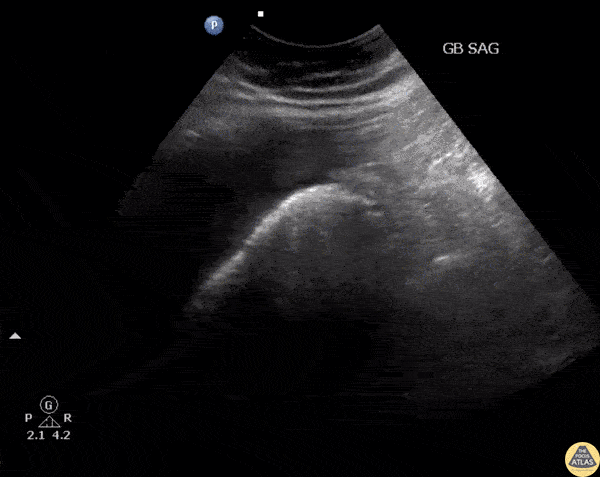

Biliary - Emphysematous Cholecystitis

RUQ US of a patient revealed air within the gallbladder consistent with emphysematous cholecystitis, which can easily be confused with bowel gas. Image courtesy of Robert Jones DO, FACEP @RJonesSonoEM Director, Emergency Ultrasound; MetroHealth Medical Center; Professor, Case Western Reserve Medical School, Cleveland, OH View his original post here